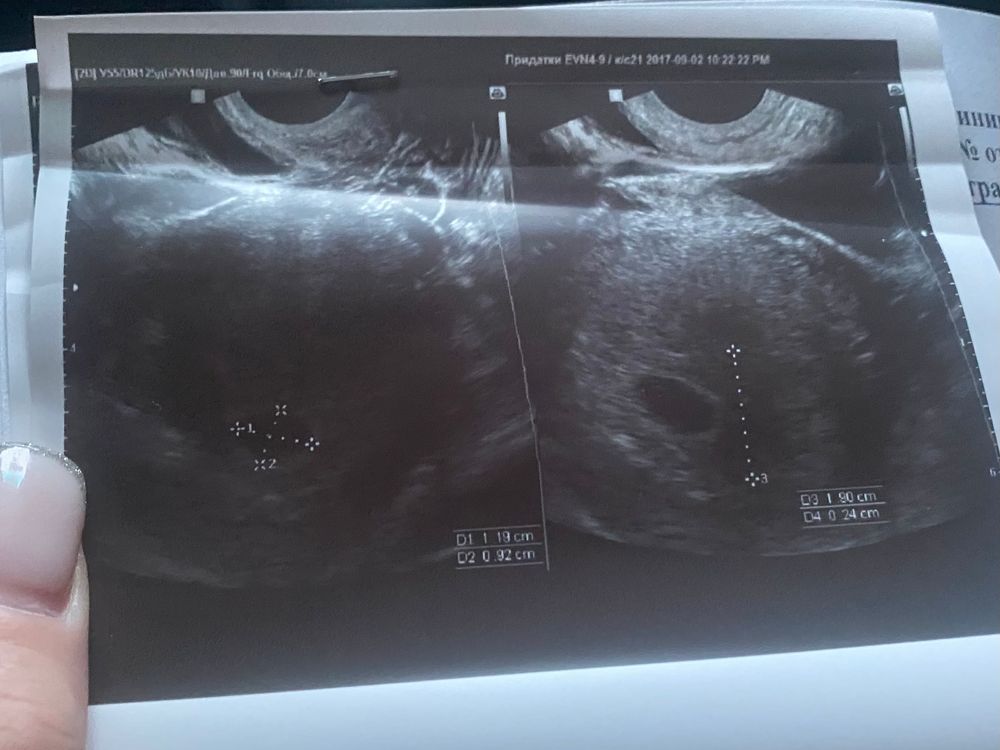

Неплохо было бы еще и описание узи прикладывать, по фото не гадают. Все зависит от вашего срока, длины цикла, когда стал полосатить тест, на какой срок намерили пя, есть ли жм. На фото не вижу желточного мешочка, нет жм =нет эмбриона